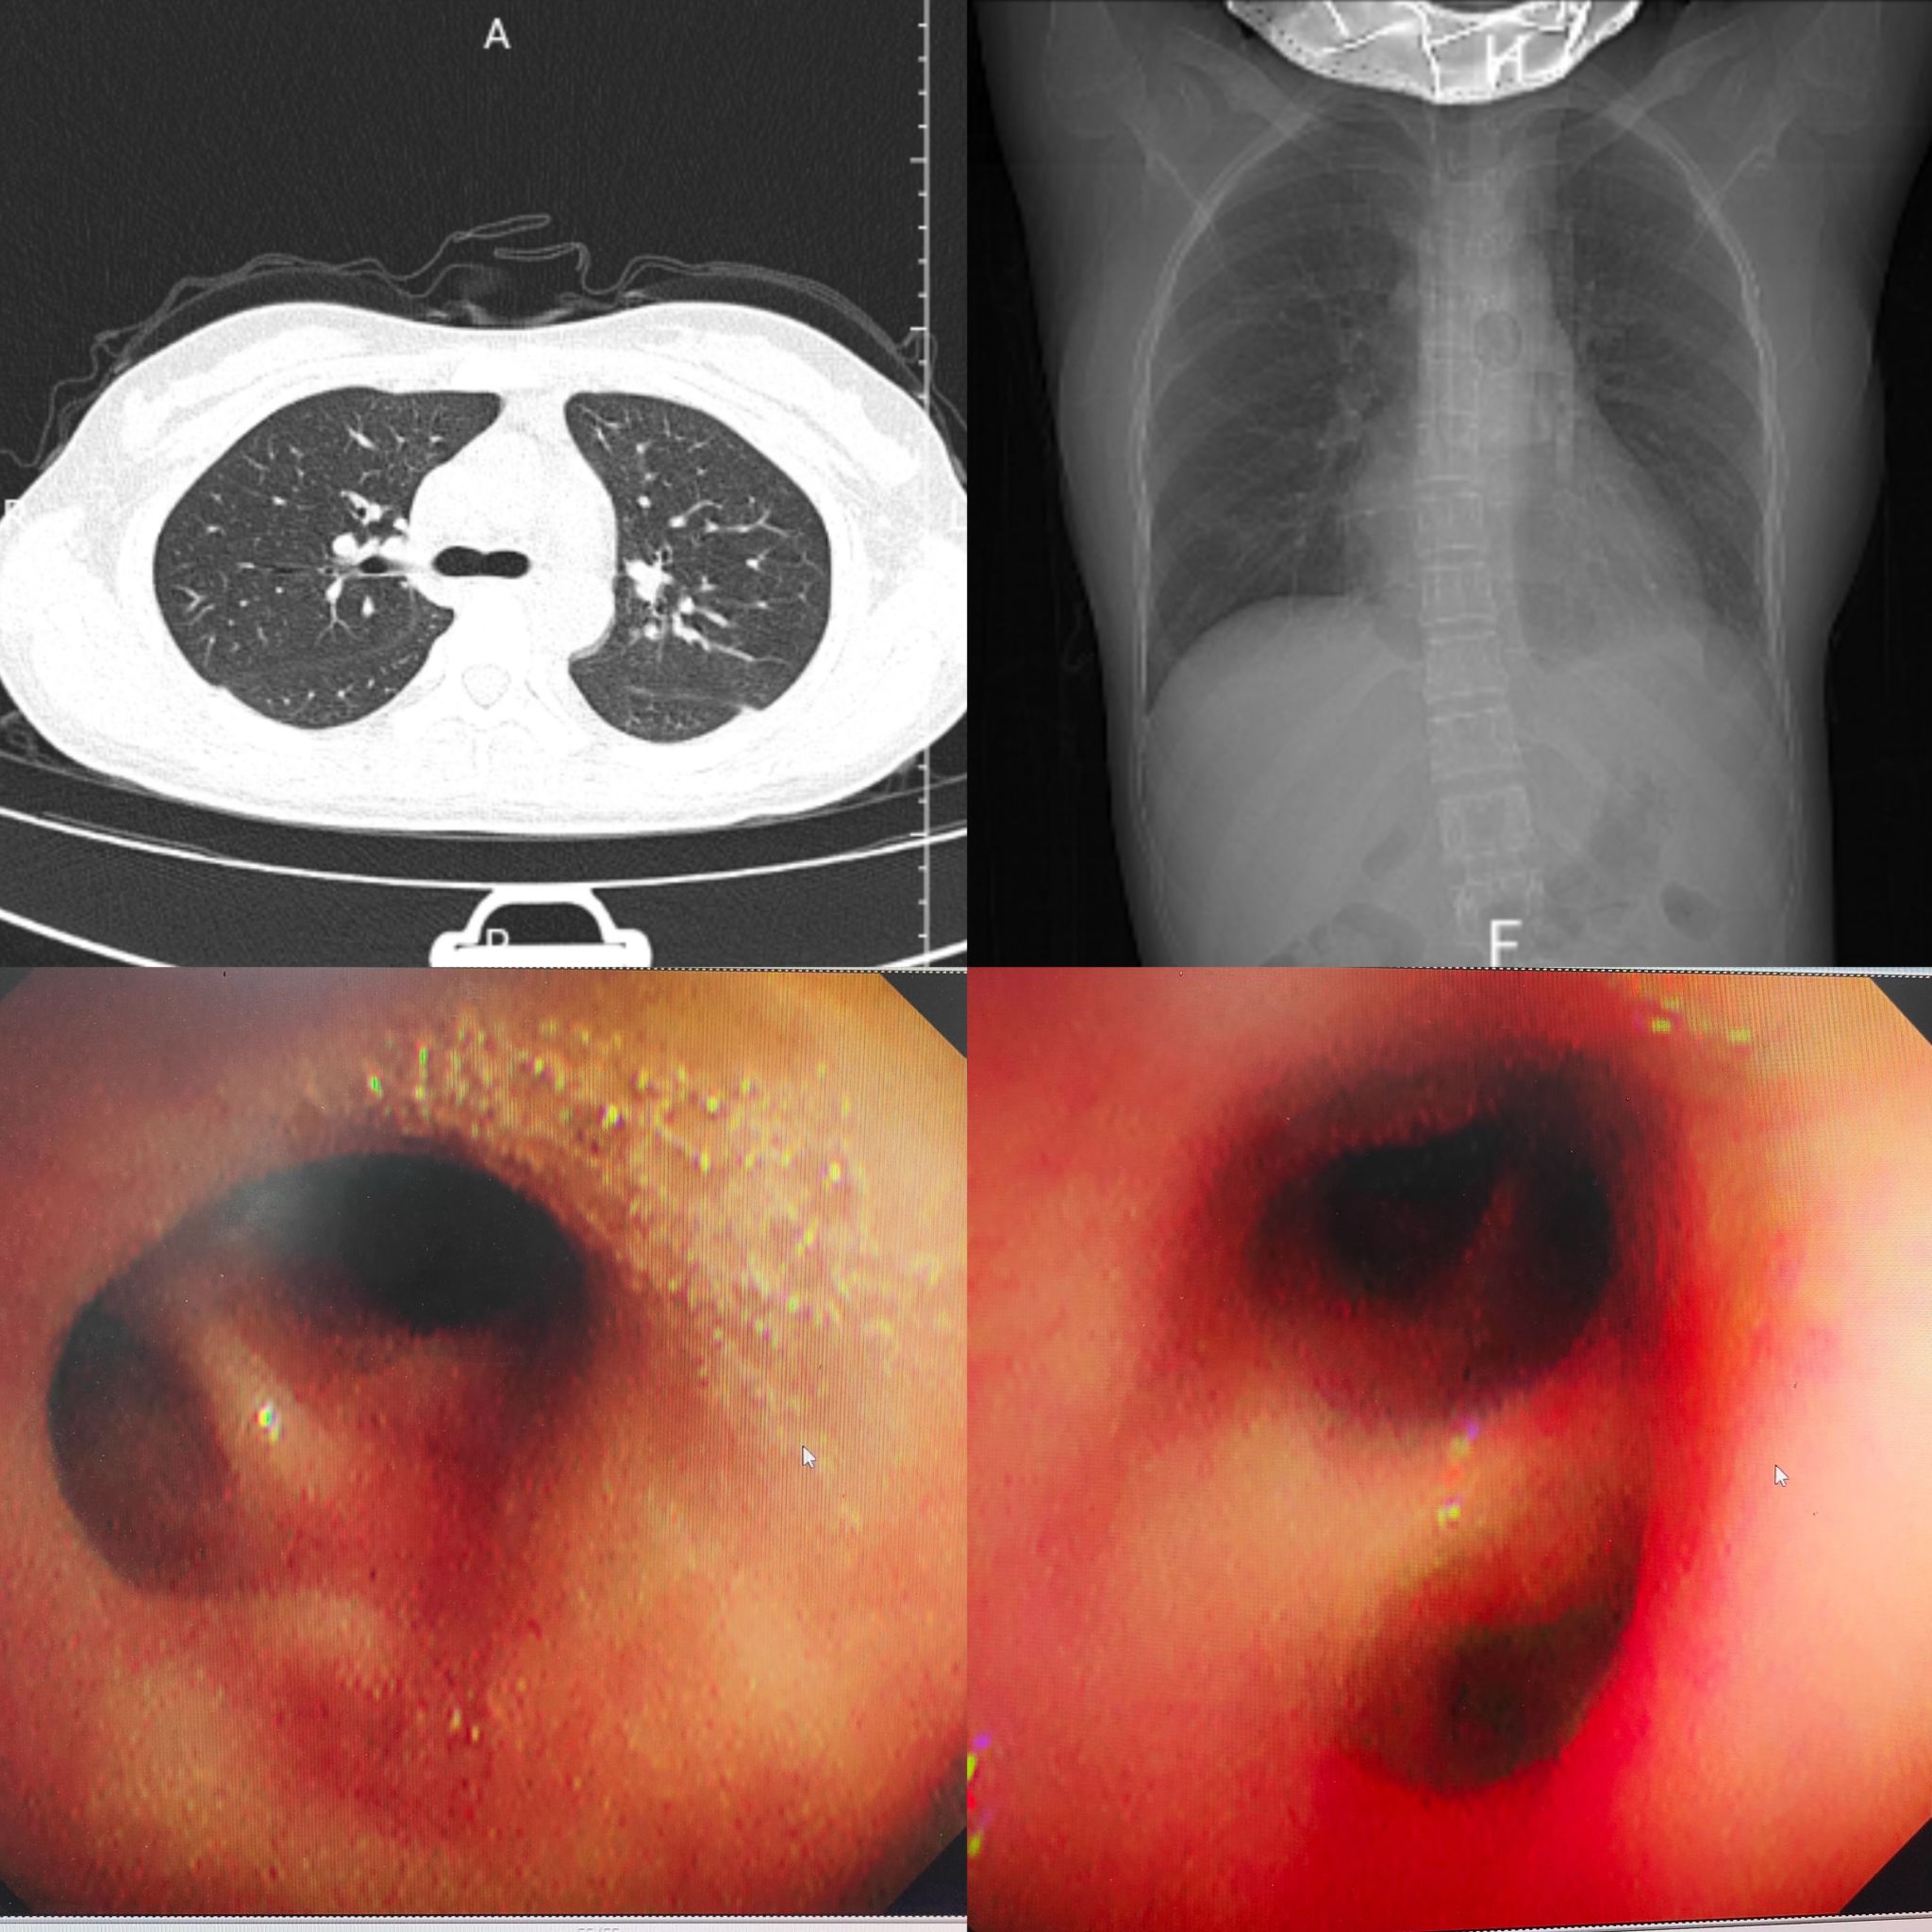

治疗后胸部CT及支气管镜下表现

经过24小时紧急救治,患儿呼吸困难症状逐渐减轻,氧合、凝血指标趋于稳定。36小时体温下降,48小时体温、凝血指标恢复正常,胸片显示胸水及实变明显吸收。120小时复查胸部CT,肺部实变、胸水基本消失。168小时各项指标均达正常水平,后续经中医巩固治疗,顺利出院。出院后,医院将对患儿实行危重症全周期随访管理,持续筑牢生命安全防线。

该病例为我院今年首例流感合并多种病原感染的重症肺炎脓毒症患儿,救治成功得益于放射科、纤支镜室等科室快速支持响应,西医与中医的有效融合,PICU科室精细化诊疗护理的协同发力。 今后,PICU全体医护人员将继续深耕专业技术领域,强化多学科联动机制,发挥中西医结合优势,用更好的技术,更优的护理为患者生命护航。(审核:张霞 杨小红)